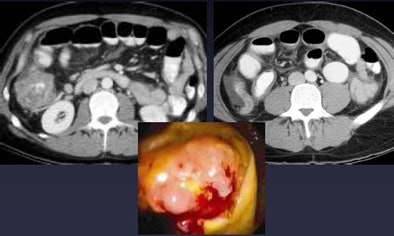

| Tumors can cause obstructive appendicitis, especially in elderly populations, as in the cecal cancer, above, causing acute appendicitis. Below, alternative diagnosis of an intussuscepted appendicele. All images courtesy of Dr. Perry Pickhardt. |